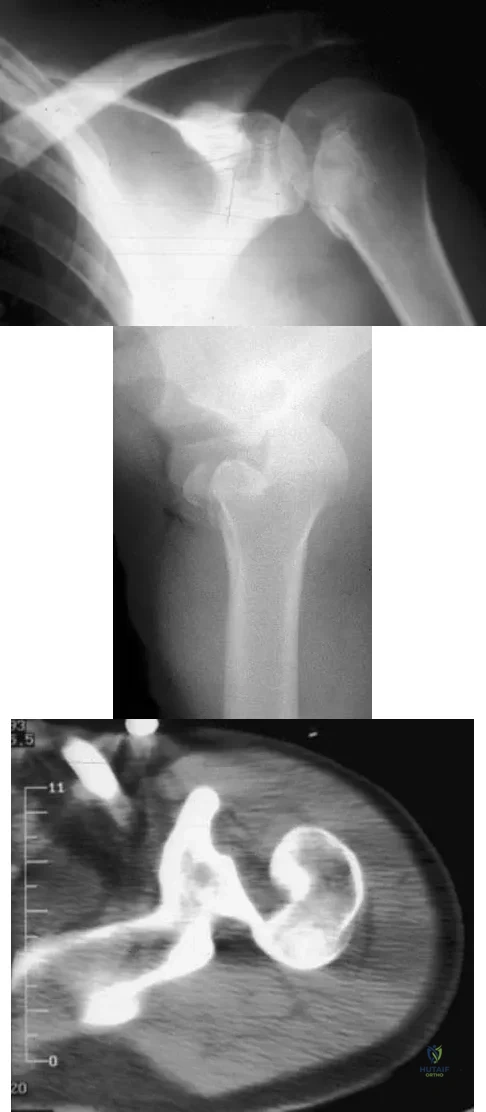

A 30-year-old right hand-dominant woman is seen in the trauma unit after a high-speed motor vehicle accident. She sustained a right shoulder anterior dislocation that is gently reduced under sedation. A CT scan is shown in Figure 3. If left untreated, the patient is at greatest risk for

Explanation

Question 70

A 21-year-old patient has had pain and a marked decrease in active and passive shoulder motion after having had a seizure 2 months ago as the result of alcohol abuse. Current AP and axillary radiographs and a CT scan are shown in Figures 26a through 26c. Management should consist of